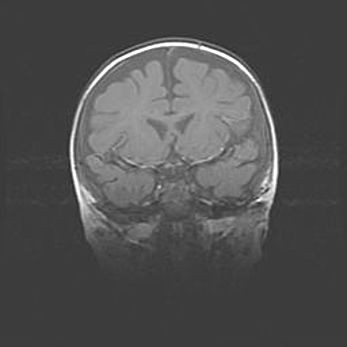

Наружная гидроцефалия с возможной атрофией височных областей.

Возраст: 28 дней

Вес: 3670 г

Пол: мужской

Окружность головы: 38 см

Срок гестации: 40 недель

Гидроцефалия головного мозга у новорожденных – это заболевание, которое характеризуется скоплением избыточного количества спинномозговой жидкости в желудочковой системе головного мозга в результате затруднения её перемещения от места выработки к месту поглощения в кровеносную систему или вследствие нарушения абсорбции. При открытой наружной форме гидроцефалии у новорожденных расширяются и переполняются субарахноидные пространства.

При нормотензивных  формах,  которые,  как  правило,  являются  следствием  перенесенных ишемических  повреждений  паренхимы  мозга,  возможно  сочетание микроцефалии  с нормотензивной гидроцефалией. В основе данных изменений лежит атрофия больших полушарий с преимущественной  локализацией  в  лобно-височных  областях.